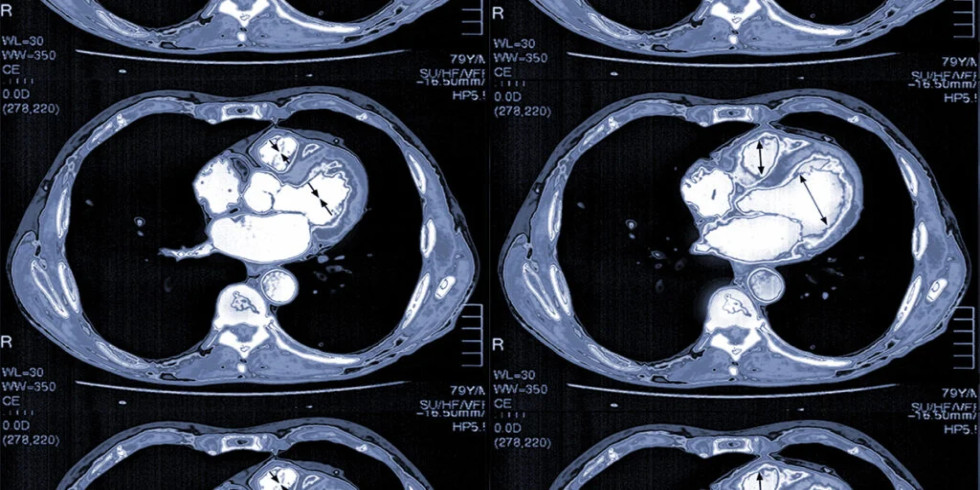

A CT coronary angiogram, also known as CTCA, is a non-invasive imaging test that uses X-rays and a contrast dye to visualize the coronary arteries and detect blockages or other abnormalities. It helps diagnose coronary artery disease by highlighting the arteries and any potential issues within them. Here's a more detailed explanation: What it is: CTCA uses a CT scanner and a contrast dye (usually iodine-based) injected into a vein, typically in the arm, to visualize the coronary arteries. The contrast dye highlights the arteries, making them appear bright on the images produced by the CT scanner, allowing doctors to see the blood flow and identify any blockages or narrowing. How it works: 1. Preparation: Patients may need to avoid eating and drinking for a certain period before the scan and may be given medication to slow their heart rate for clearer images. 2. IV Insertion: An intravenous line (IV) is inserted into a vein, usually in the arm, to administer the contrast dye. 3. Scanning: The patient lies on a table that moves into the CT scanner (a doughnut-shaped machine). The scanner rotates around the patient, taking multiple X-ray images. 4. Image Acquisition: The contrast dye highlights the coronary arteries, allowing doctors to evaluate their structure and identify any blockages, plaque buildup, or other abnormalities. 5. Post-Procedure: Patients can usually resume normal activities immediately after the scan, but may be advised to drink plenty of fluids to help flush out the contrast dye. Purpose: Detect Blockages: CTCA is used to identify blockages or narrowing (stenosis) of the coronary arteries, which can be a sign of coronary artery disease. Assess Plaque Buildup: It can detect the presence and extent of plaque buildup (atherosclerosis) in the arteries, which can restrict blood flow. Evaluate Heart Disease Risk: CTCA helps assess the overall risk of heart disease and can guide treatment decisions. Guide Further Procedures: If significant blockages are found, CTCA can help determine if further procedures like angioplasty or bypass surgery are needed. Potential Risks: Allergic Reaction: A small percentage of patients may experience an allergic reaction to the contrast dye, ranging from mild (itching, hives) to severe (difficulty breathing, anaphylaxis). Kidney Problems: In rare cases, contrast dye can potentially harm the kidneys, especially in patients with pre-existing kidney conditions. Radiation Exposure: CTCA involves exposure to X-ray radiation, but the dose is generally considered low and safe for most patients.